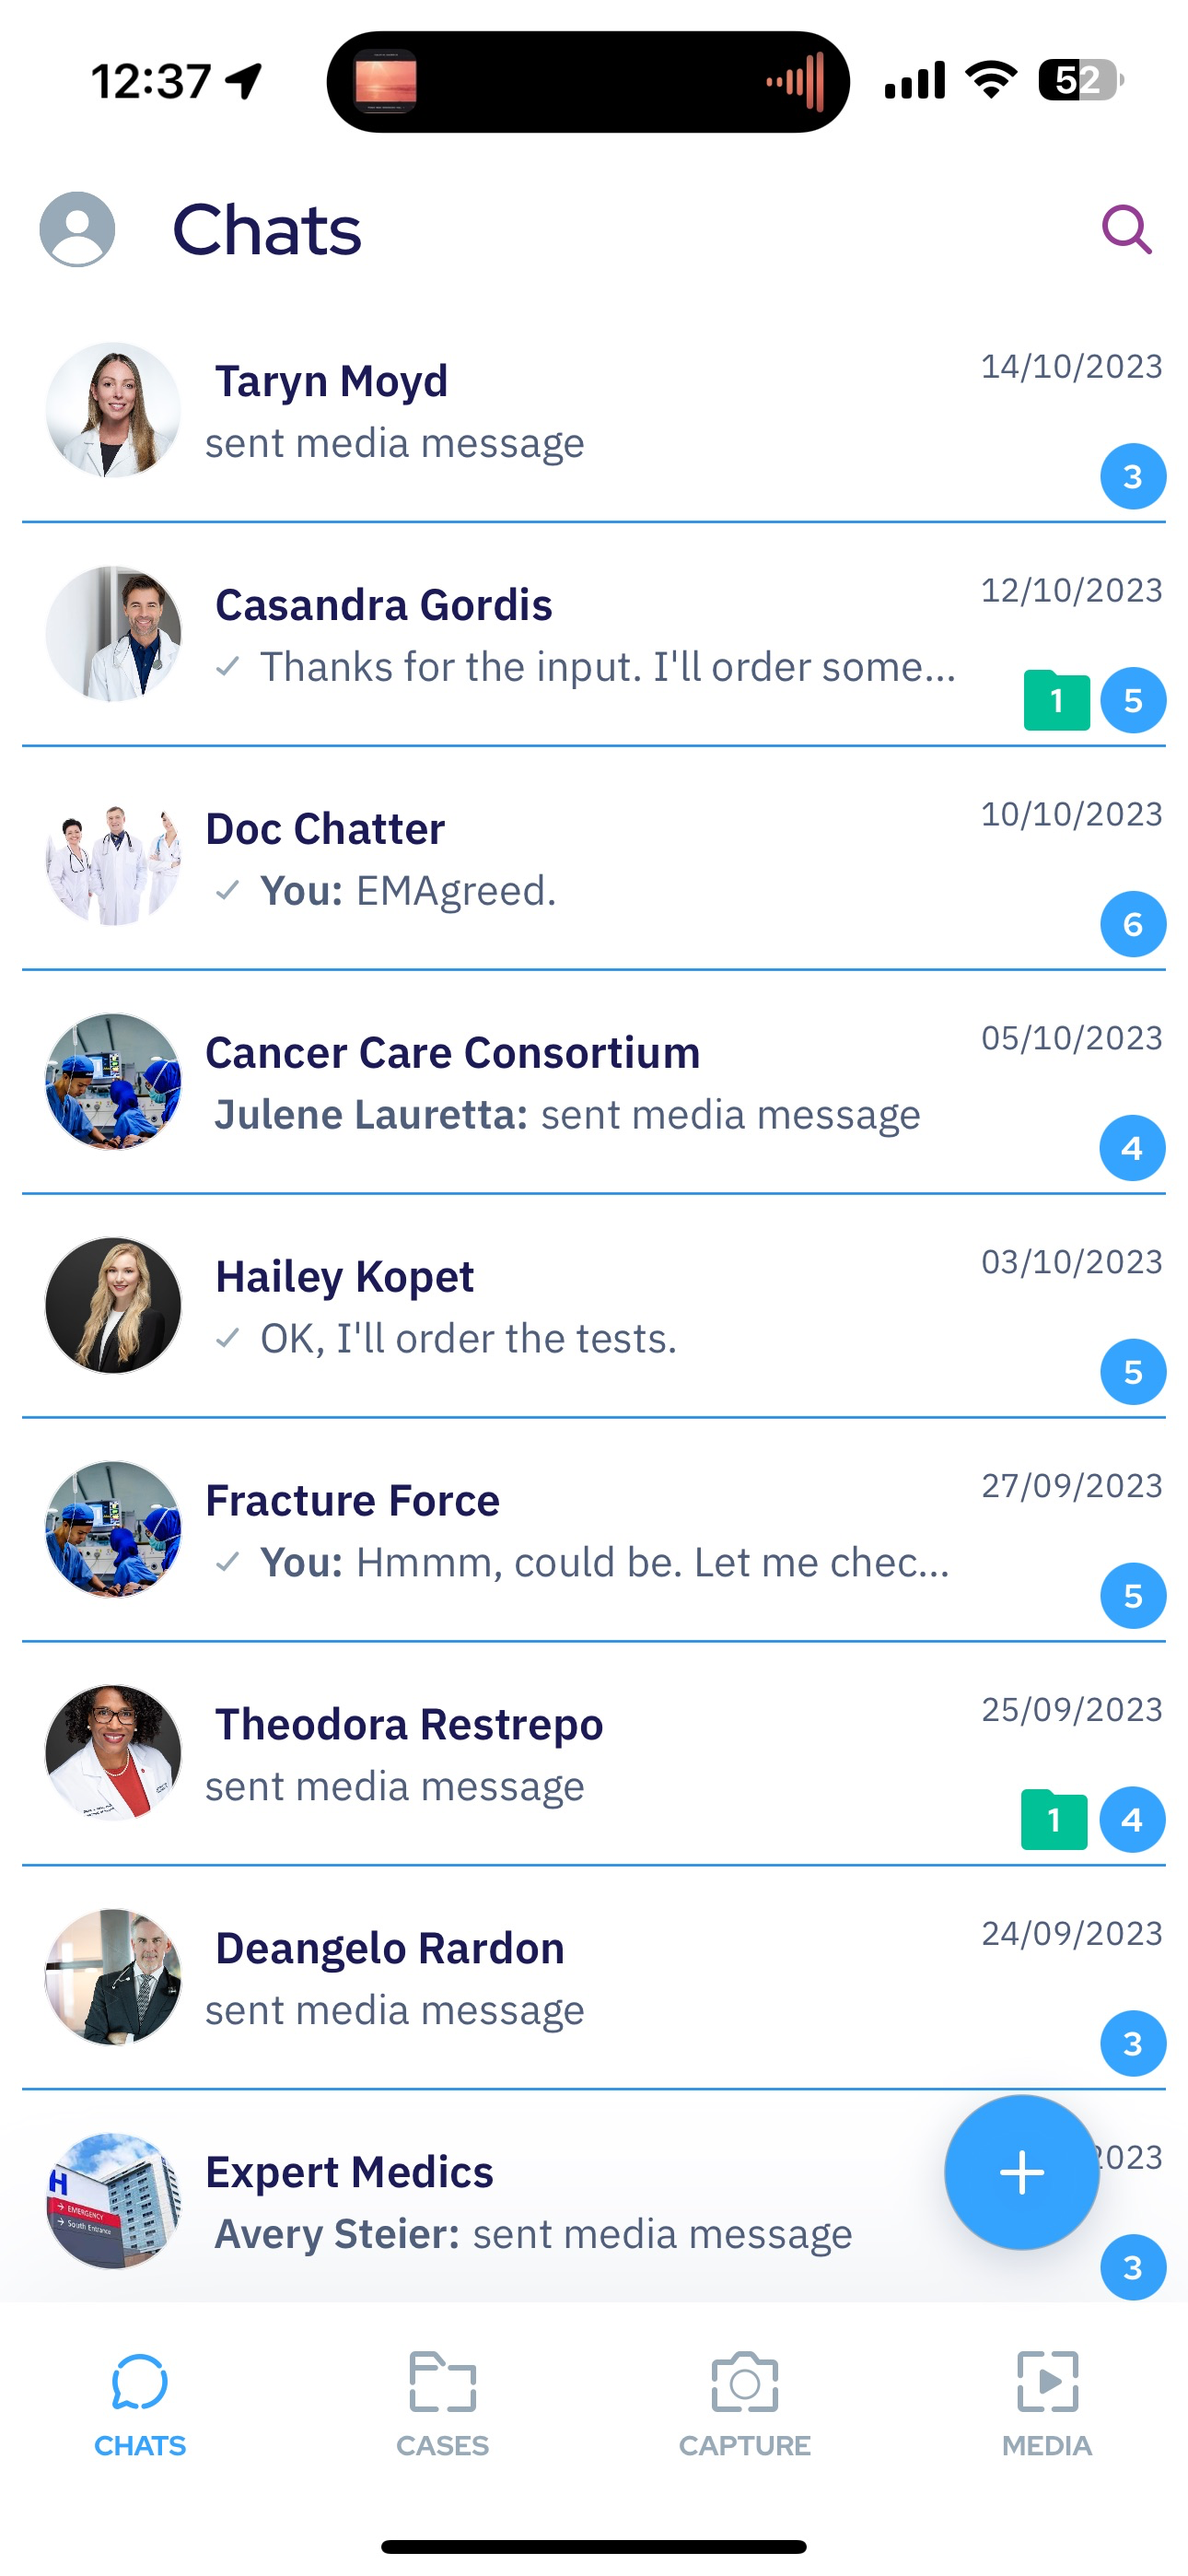

SeaGreen is a secure, open, free to use platform for healthcare professional to connect and collaborate. SeaGreen streamline consultation and collaboration such as AI powered capture mode that anonymize and a software virtual operating room.